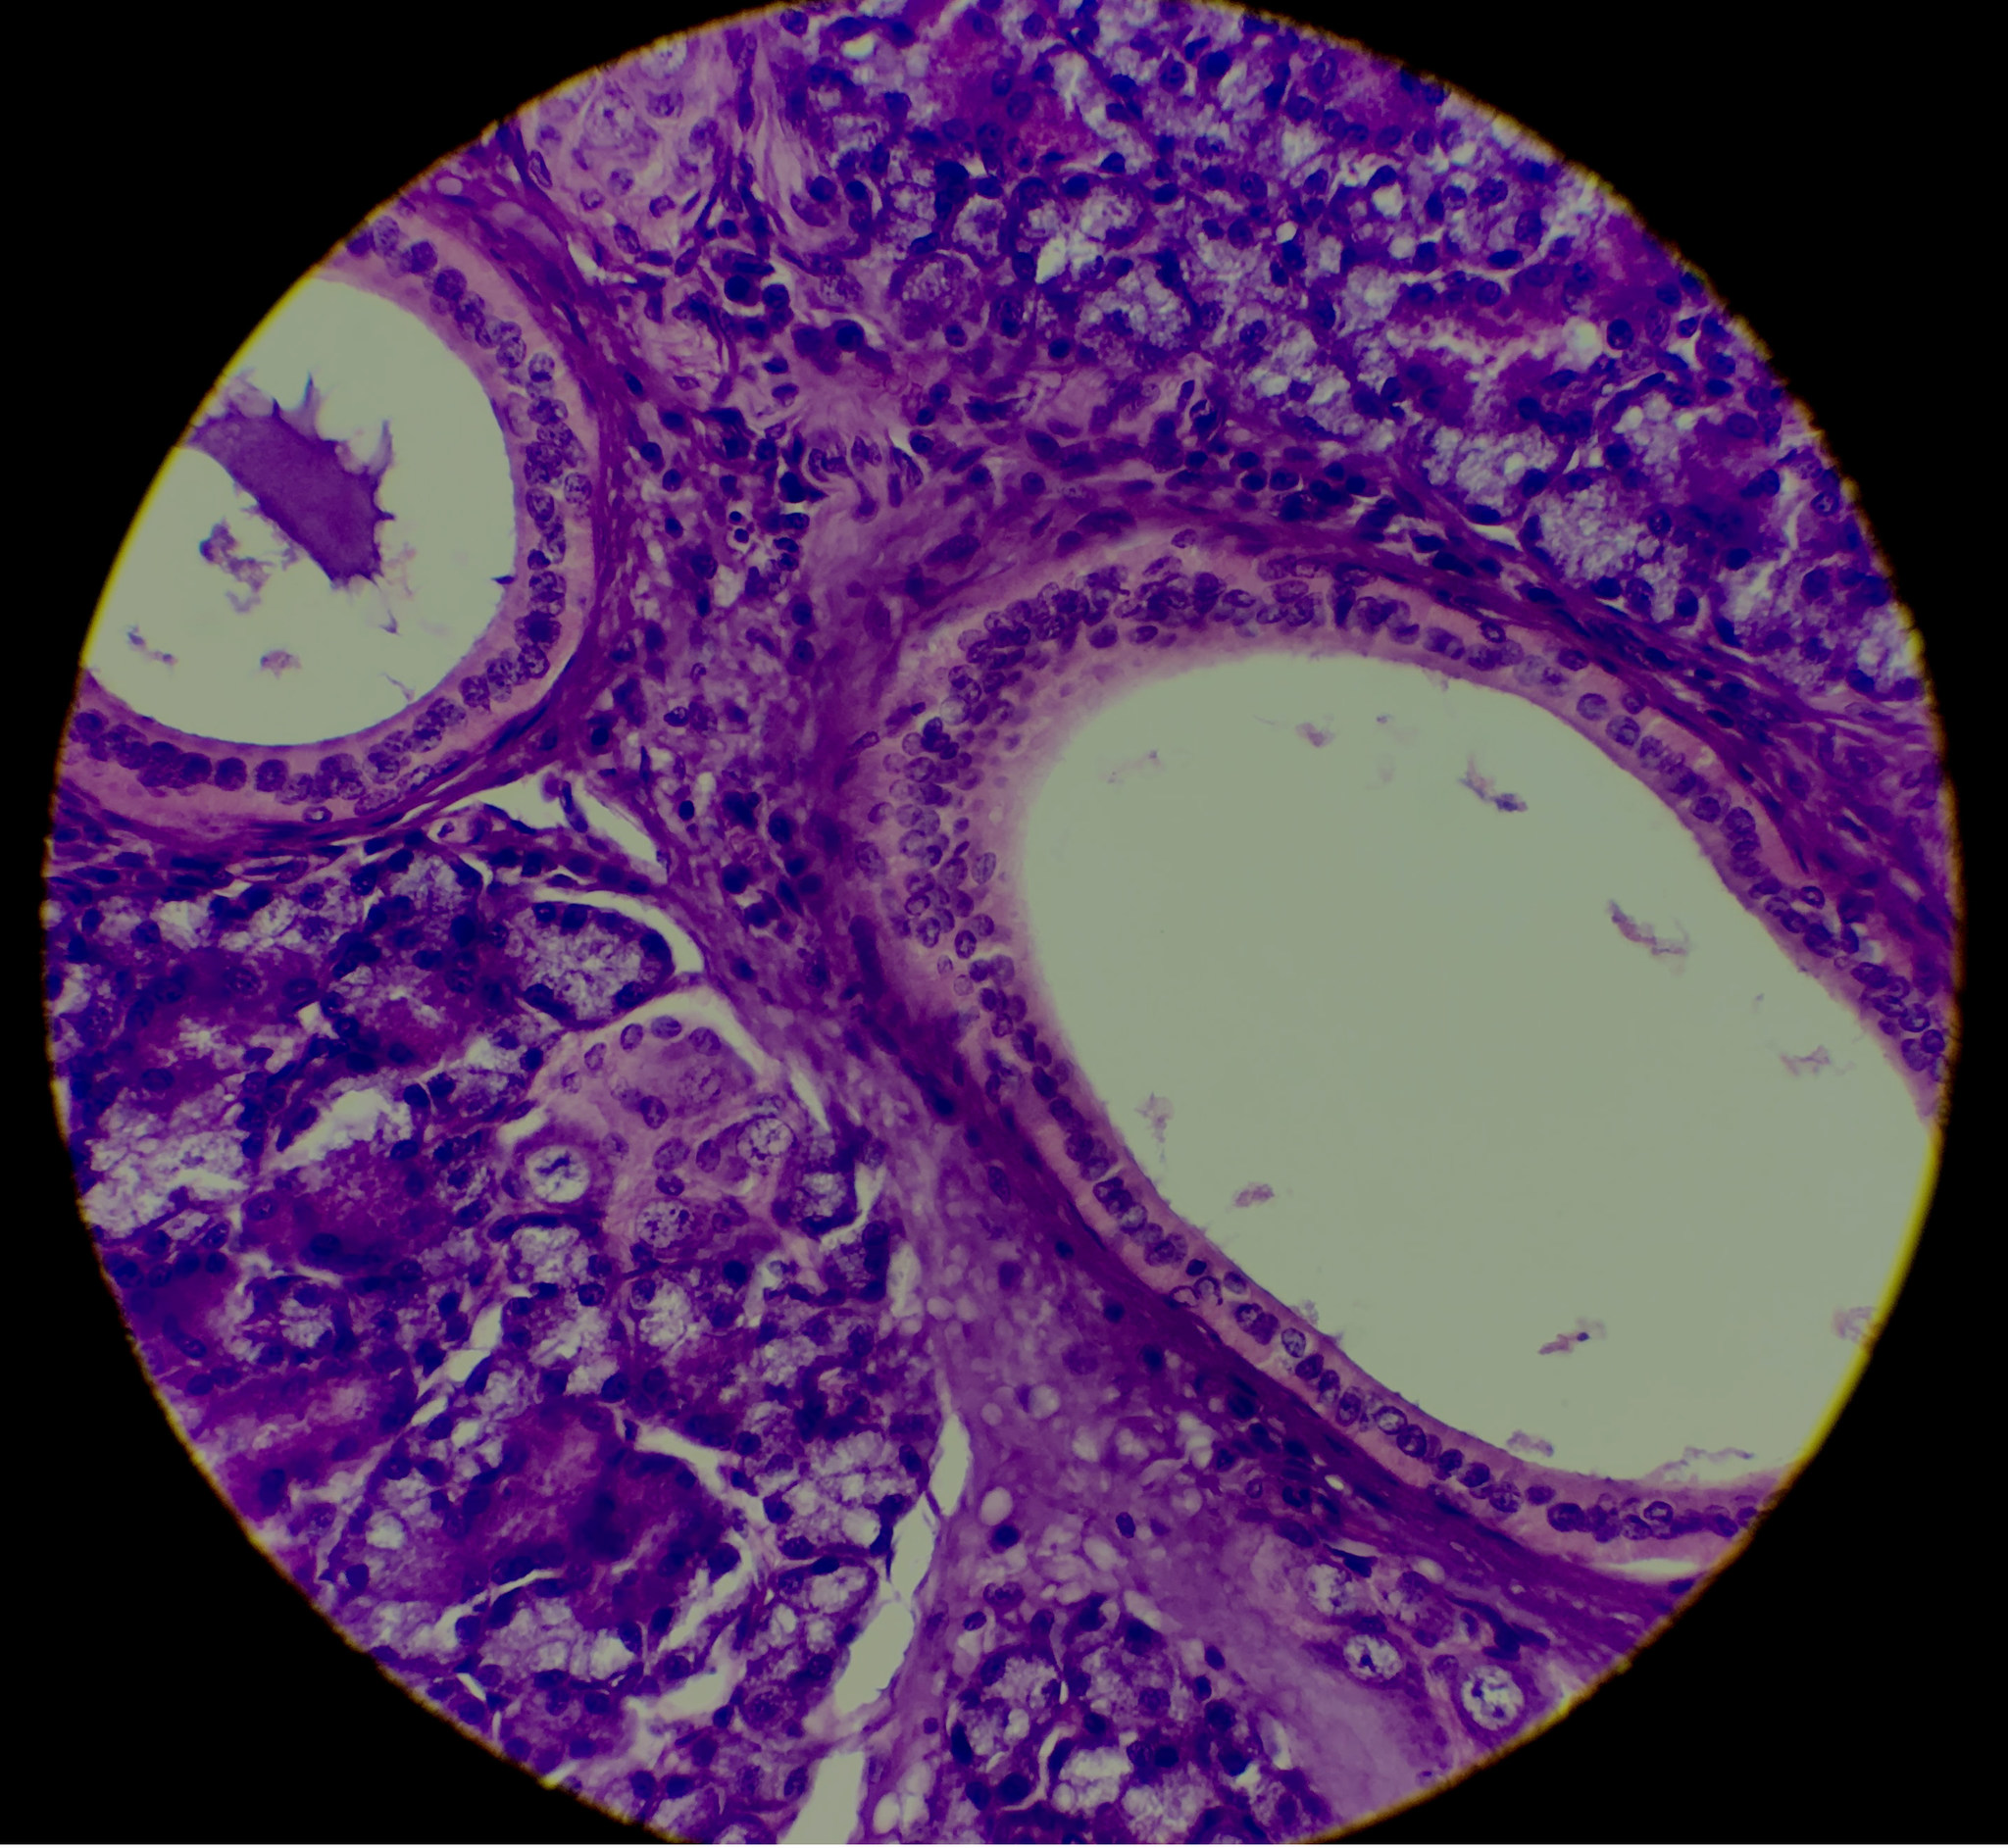

Salivary Gland, Edited, 1000x, Simple Cuboidal Epithelium